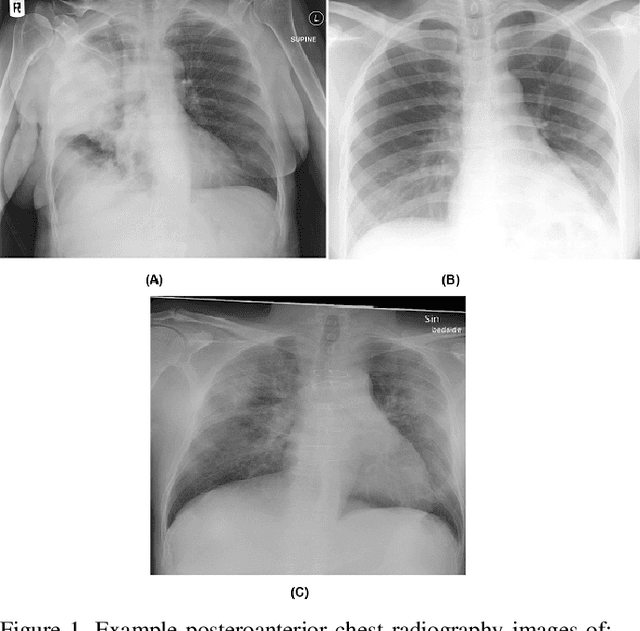

Abstract:Background: A critical step in effective care and treatment planning for severe acute respiratory syndrome coronavirus 2 (SARS-CoV-2) is the assessment of the severity of disease progression. Chest x-rays (CXRs) are often used to assess SARS-CoV-2 severity, with two important assessment metrics being extent of lung involvement and degree of opacity. In this proof-of-concept study, we assess the feasibility of computer-aided scoring of CXRs of SARS-CoV-2 lung disease severity using a deep learning system. Materials and Methods: Data consisted of 130 CXRs from SARS-CoV-2 positive patient cases from the Cohen study. Geographic extent and opacity extent were scored by two board-certified expert chest radiologists (with 20+ years of experience) and a 2nd-year radiology resident. The deep neural networks used in this study are based on a COVID-Net network architecture. 100 versions of the network were independently learned (50 to perform geographic extent scoring and 50 to perform opacity extent scoring) using random subsets of CXRs from the Cohen study, and evaluated the networks using stratified Monte Carlo cross-validation experiments. Findings: The deep neural networks yielded R$^2$ of 0.673 $\pm$ 0.004 and 0.636 $\pm$ 0.002 between predicted scores and radiologist scores for geographic extent and opacity extent, respectively, in stratified Monte Carlo cross-validation experiments. The best performing networks achieved R$^2$ of 0.865 and 0.746 between predicted scores and radiologist scores for geographic extent and opacity extent, respectively. Interpretation: The results are promising and suggest that the use of deep neural networks on CXRs could be an effective tool for computer-aided assessment of SARS-CoV-2 lung disease severity, although additional studies are needed before adoption for routine clinical use.

Abstract:The COVID-19 pandemic continues to have a devastating effect on the health and well-being of the global population. A critical step in the fight against COVID-19 is effective screening of infected patients, with one of the key screening approaches being radiological imaging using chest radiography. Motivated by this, a number of artificial intelligence (AI) systems based on deep learning have been proposed and results have been shown to be quite promising in terms of accuracy in detecting patients infected with COVID-19 using chest radiography images. However, to the best of the authors' knowledge, these developed AI systems have been closed source and unavailable to the research community for deeper understanding and extension, and unavailable for public access and use. Therefore, in this study we introduce COVID-Net, a deep convolutional neural network design tailored for the detection of COVID-19 cases from chest X-ray (CXR) images that is open source and available to the general public. We also describe the CXR dataset leveraged to train COVID-Net, which we will refer to as COVIDx and is comprised of 13,800 chest radiography images across 13,725 patient patient cases from three open access data repositories, one of which we introduced. Furthermore, we investigate how COVID-Net makes predictions using an explainability method in an attempt to gain deeper insights into critical factors associated with COVID cases, which can aid clinicians in improved screening. By no means a production-ready solution, the hope is that the open access COVID-Net, along with the description on constructing the open source COVIDx dataset, will be leveraged and build upon by both researchers and citizen data scientists alike to accelerate the development of highly accurate yet practical deep learning solutions for detecting COVID-19 cases and accelerate treatment of those who need it the most.